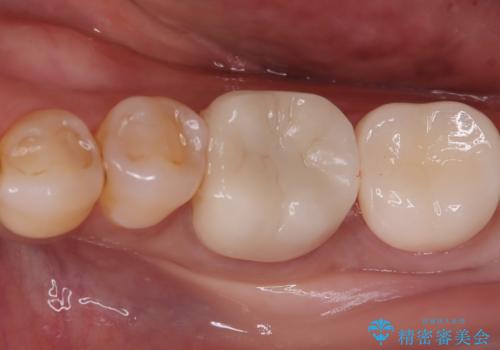

まず左下6番のヒビや弱くなった部分を除去し、セラミッククラウンが適切に装着できる形に整えました。隣接する7番についても同様に支台形成を行い、両方の歯を連続して補強する形としました。クラウンは、見た目の自然さと耐久性を兼ね備えたセラミックを選択し、咬合圧に配慮したデザインと高さ調整を丁寧に行いました。

また、ブラッシング時に不快感があった左下の親知らずは、炎症や清掃障害の原因になることから、治療前に抜歯しました。クラウン装着後は、違和感や痛みもなく、噛むときの安定感が向上。患者さんからは「しっかり噛めるようになって安心した」とご感想をいただきました。今後は定期的なメンテナンスで状態を保っていきます。